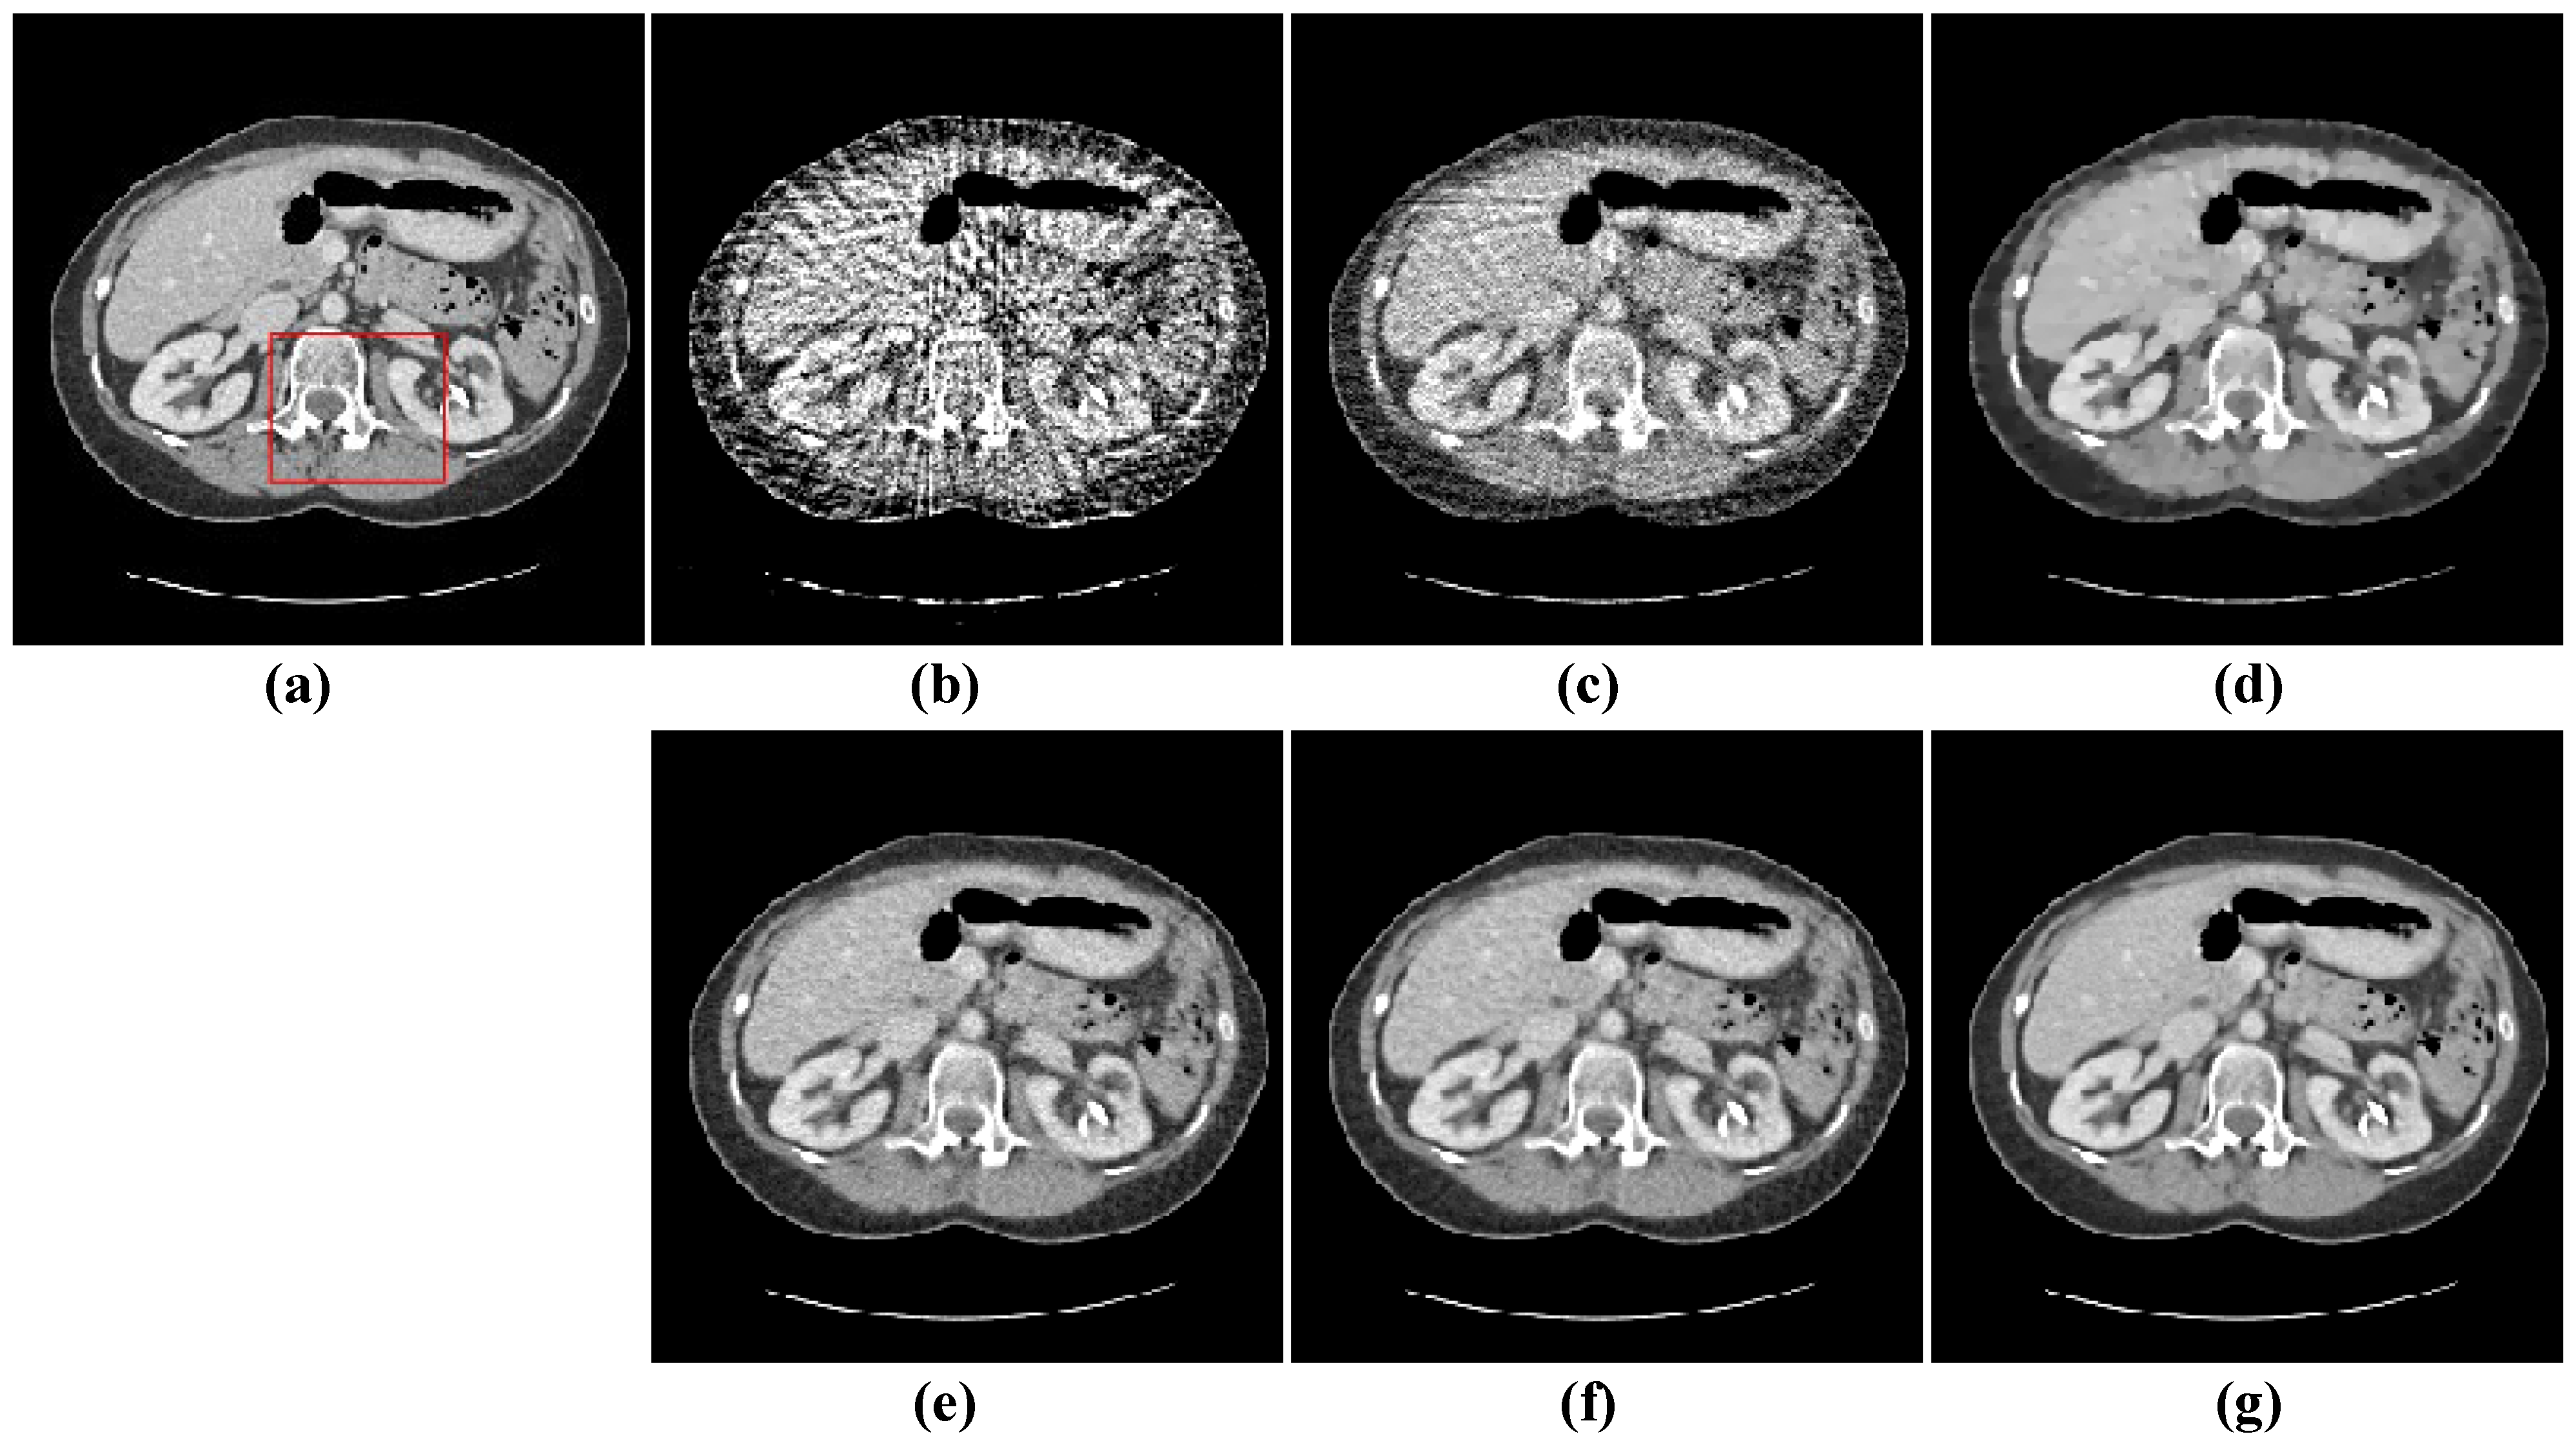

4.2. Image Reconstruction Experiment of Abdomen Image

| Views | 48 | 64 | 80 | |||||||

|---|---|---|---|---|---|---|---|---|---|---|

| Algorithm | RMSE | PSNR | SSIM | RMSE | PSNR | SSIM | RMSE | PSNR | SSIM | |

| FBP | 0.0572 | 24.8531 | 0.3877 | 0.0532 | 25.4793 | 0.4416 | 0.0490 | 26.2008 | 0.4898 | |

| OS-SART | 0.0194 | 32.2530 | 0.8487 | 0.0163 | 33.7509 | 0.8758 | 0.0140 | 35.1534 | 0.8987 | |

| TV | 0.0149 | 35.0197 | 0.8911 | 0.0113 | 36.6015 | 0.9075 | 0.0108 | 37.8124 | 0.9103 | |

| PICCS | 0.0102 | 38.0374 | 0.9158 | 0.0098 | 39.0875 | 0.9237 | 0.0082 | 40.2468 | 0.9304 | |

| TVPI-G | 0.0091 | 39.4513 | 0.9276 | 0.0080 | 40.3687 | 0.9335 | 0.0068 | 41.8053 | 0.9489 | |

| NPICCS | 0.0078 | 40.5177 | 0.9383 | 0.0065 | 41.9674 | 0.9508 | 0.0050 | 43.0232 | 0.9612 | |